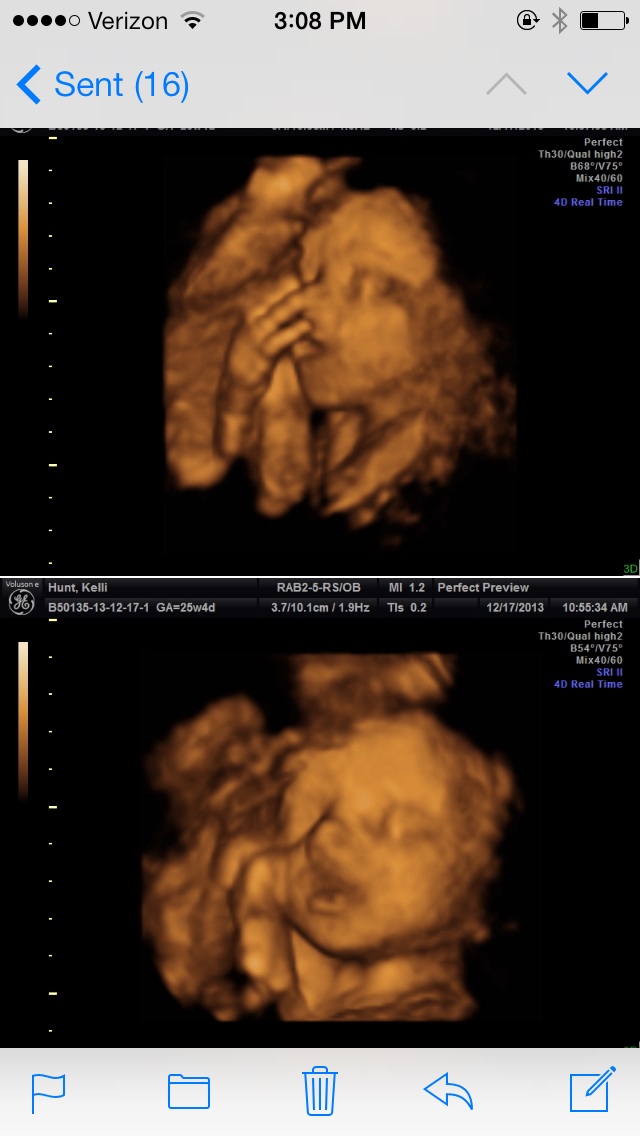

My babester looks ridiculously like my DH in this first pic. Same exact nose! (My hubby feels bad for baby but I think it's freakin adorable!) The second pic is baby's face, feet and hand...he/she had it's feet by it's face through most of the u/s, grabbing and playing with them This was at 24wks, 4 wks ago!

The second pic is baby's face, feet and hand...he/she had it's feet by it's face through most of the u/s, grabbing and playing with them

This was at 24wks, 4 wks ago!